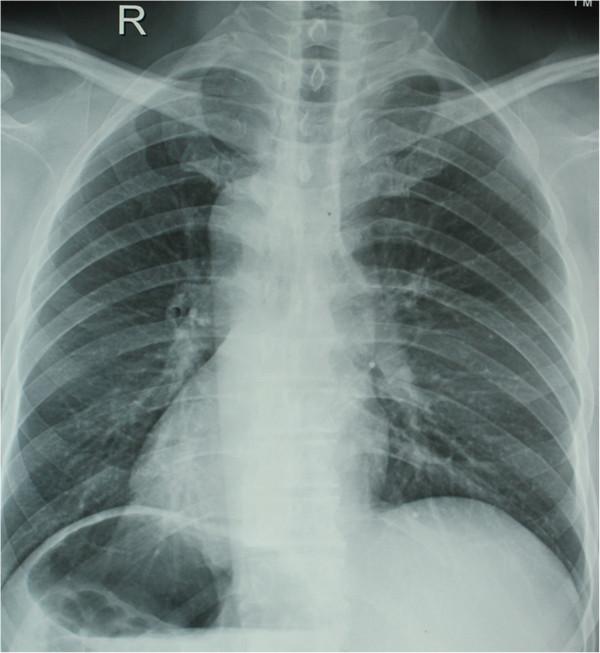

Situs inversus is an uncommon anomaly with rare incidence. Some cases of situs inversus totalis have been described with different types of associations. Here we report a case of situs inversus with carcinoma of the gastric cardia.

situs inversus 是一种罕见的异常,发病率很低。有些 situs inversus totalis 的病例伴有不同类型的合并症。在这里,我们报告一例 situs inversus 伴贲门癌。